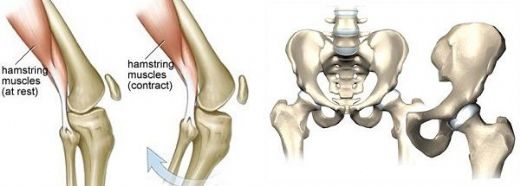

Kemik zarı, iki ana katmandan oluşur: dış fibroz katman ve iç kambiyum katman.

• Dış fibroz katman: Bu katman, yoğun bağ dokusundan oluşur ve kemik yüzeyine sağlamlık kazandırır. Ayrıca, kemik zarı ile çevresindeki dokular arasında bir bütünlük sağlar.

• İç kambiyum katman: Bu katman ise osteoblast (kemik yapıcı hücreler) ve osteoklast (kemik yıkıcı hücreler) gibi hücreleri içerir. Bu hücreler, kemik dokusunun yenilenmesi ve onarımı sürecinde önemli rol oynar.